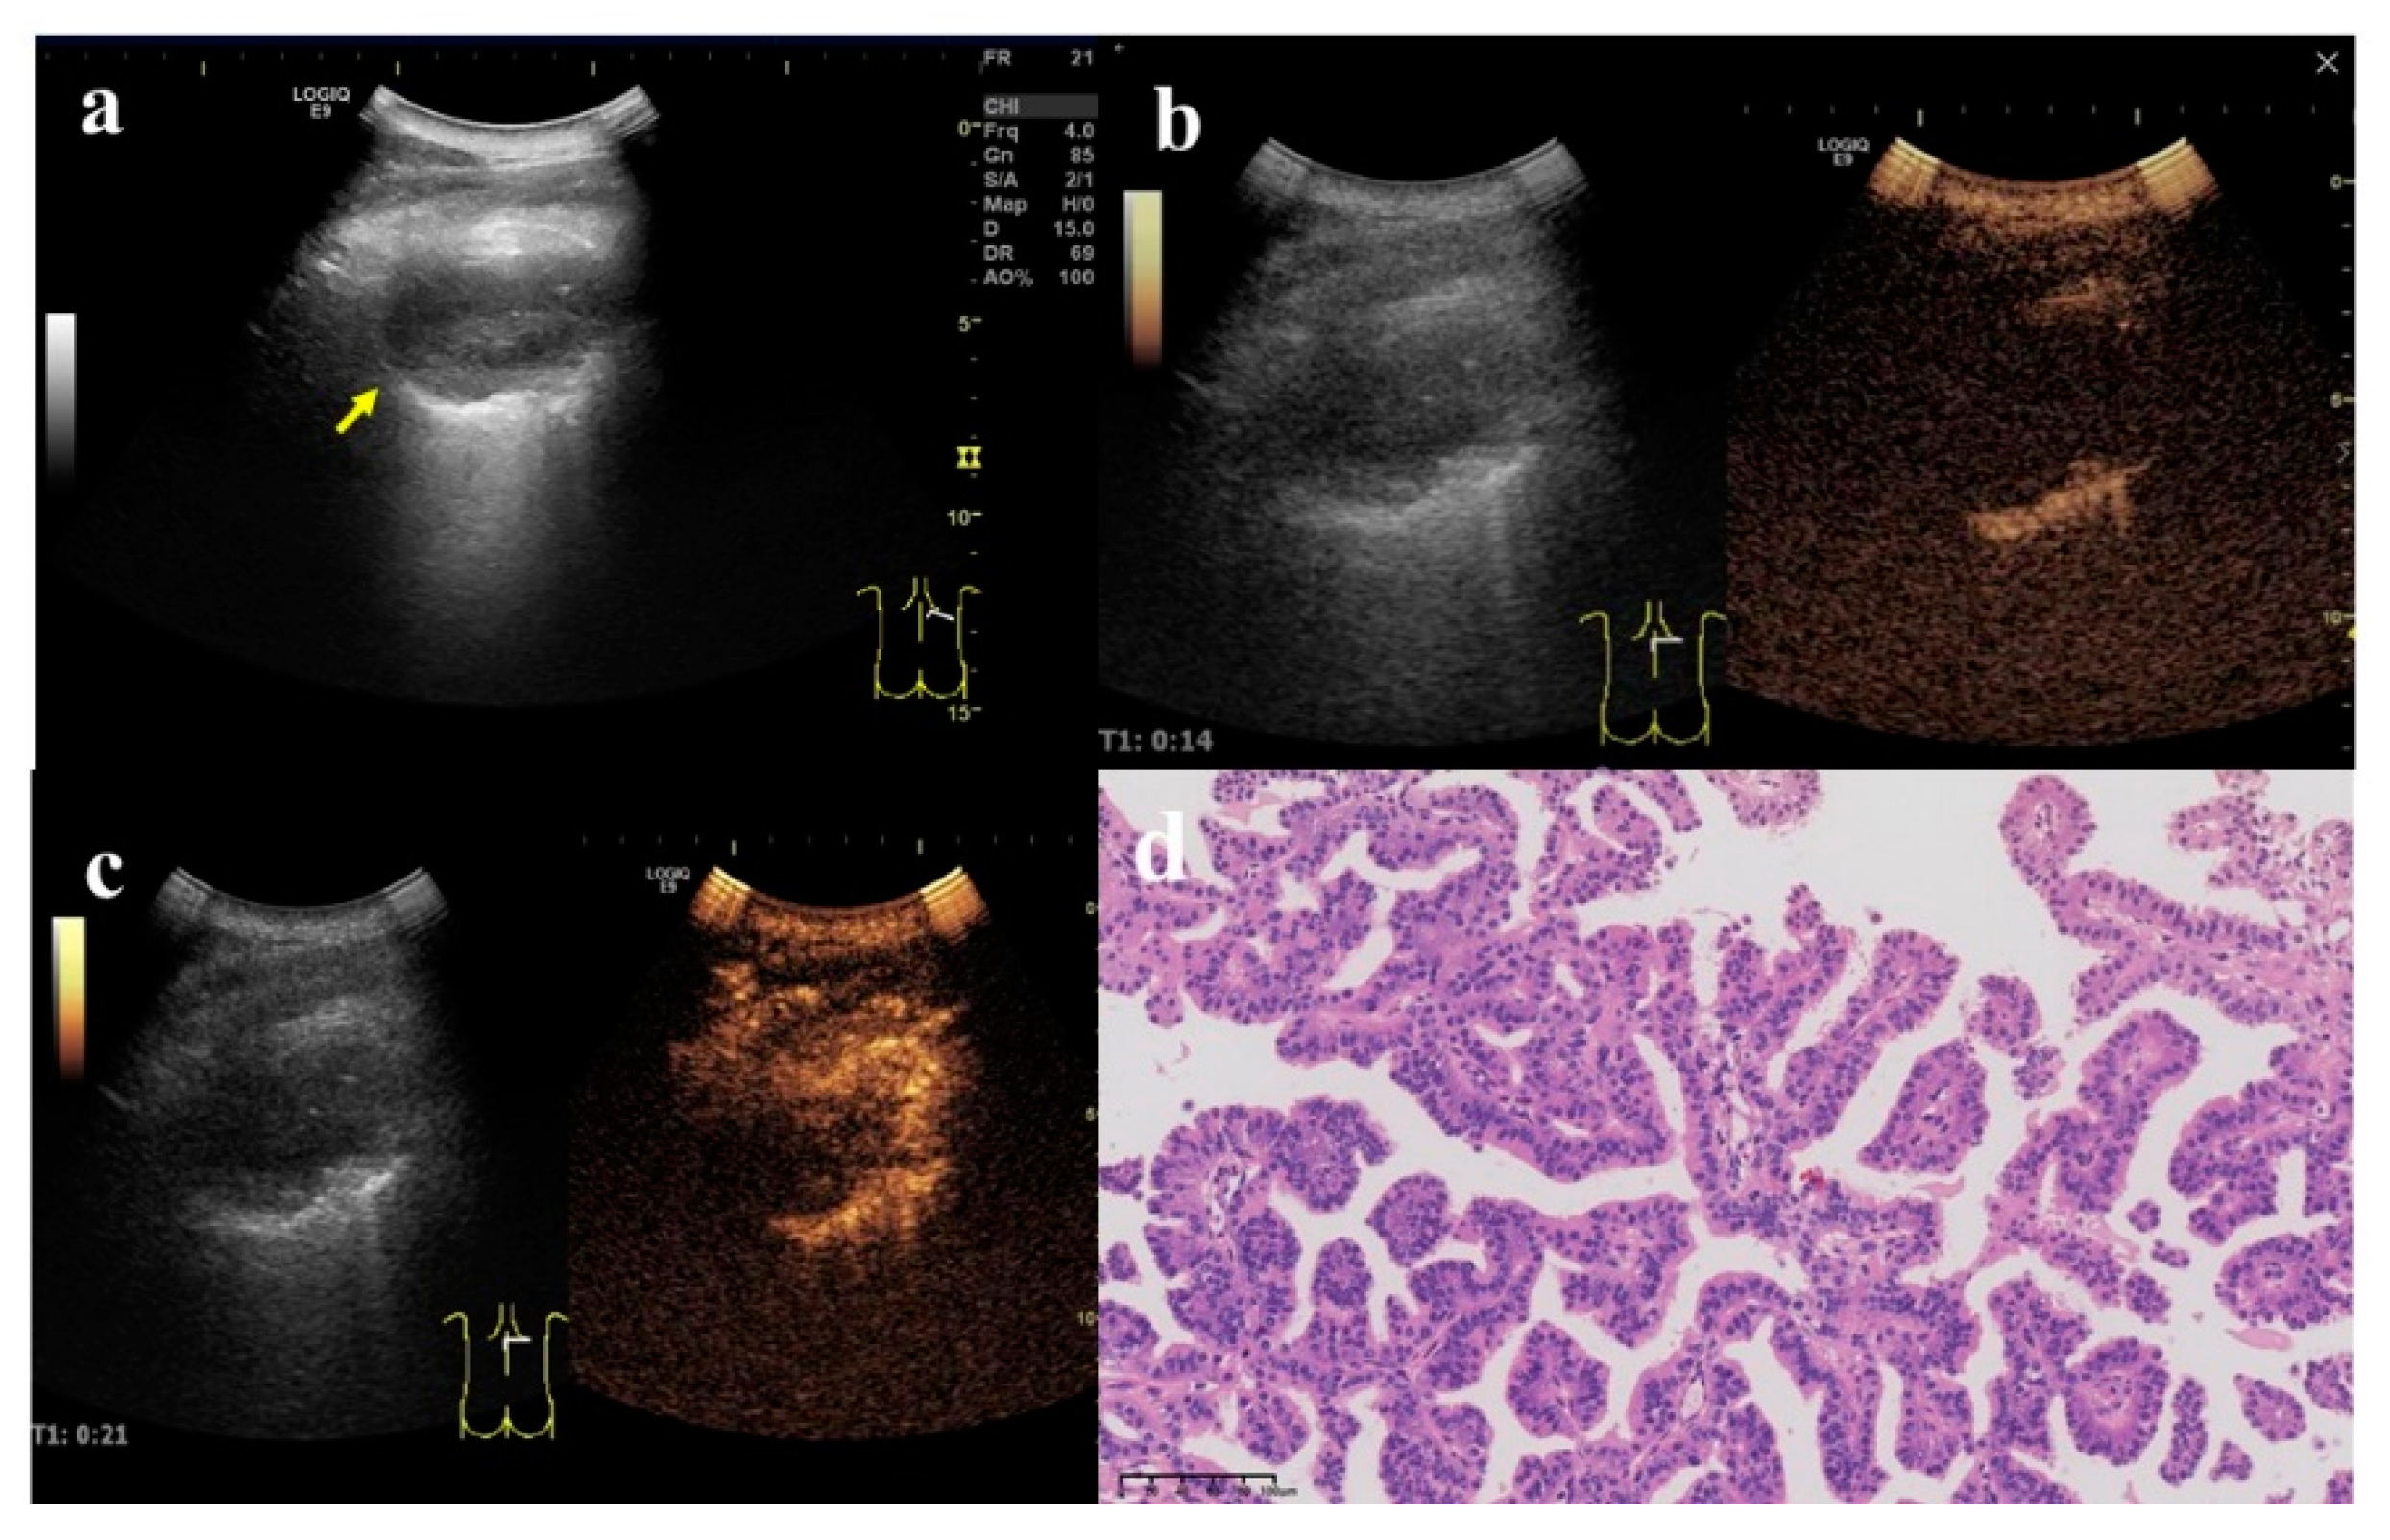

Figure 5.

A 58-year-old male with a lesion occupying the deep space in the lower corner of the right shoulder armor. (a) Two-dimensional ultrasound showed a hypoechoic nodule, size 5.5 × 4.5 cm (arrow). At least one angle (between lesion border and thoracic wall) was obtuse. (b) Contrast-enhanced ultrasound showed that the enhancement time of lung tissue was 10 s and that of nodule was 14 s. (c) The enhancement began from the periphery to the center. The enhancement reached the peak in 30 s, and the enhancement degree was obviously uneven. (d) Pathologic evaluations revealed lung adenocarcinoma, mainly solid and acinar (×200).